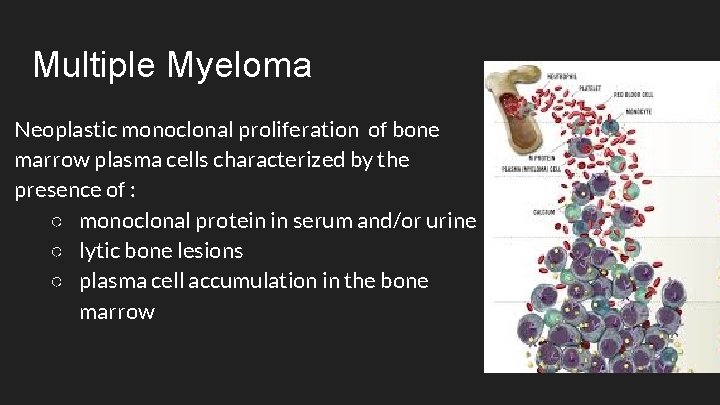

Multiple Myeloma Neoplastic monoclonal proliferation of bone marrow plasma cells characterized by the presence of : ○ monoclonal protein in serum and/or urine ○ lytic bone lesions ○ plasma cell accumulation in the bone marrow

Multiple Myeloma ● When there are multiple plasmacytomas inside or outside bone, this condition is also called multiple myeloma. ○ Plasmacytomas are localized tumors composed of plasma cells, which can grow intramedullary, extramedullary or soft-tissue.